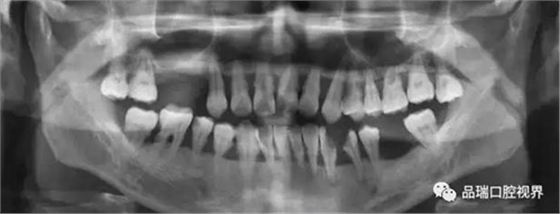

刷牙出血、牙齦紅腫、疼痛,這種情況幾乎人人都有過。在疲勞、生活不規(guī)律,刷牙潦草時(shí)更容易出現(xiàn)。很多朋友以為牙齦出血是因?yàn)槿狈δ撤N維生素。其實(shí),雖然長期嚴(yán)重缺乏維生素C確實(shí)會(huì)導(dǎo)致牙齦出血紅腫,但除非一連兩三個(gè)月都不吃蔬菜水果牛奶等含有維生素C的食物,否則,除了極少數(shù)人是由于血液病等全身疾病,絕大多數(shù)牙齦出血都是牙齦炎的表現(xiàn)。牙齦出血,原因多為牙齦炎或牙周炎。

牙周炎是一種漸進(jìn)性的疾病——就是說它并不會(huì)像普通感冒一樣,不管治不治療,只要不繼發(fā)感染,一周左右都會(huì)好。如果不對(duì)炎癥和口腔的刺激因素進(jìn)行控制,牙齦炎會(huì)進(jìn)一步發(fā)展為牙周炎,這就不再是僅限于軟組織的炎癥,而是會(huì)累及牙槽骨,當(dāng)骨質(zhì)緩慢喪失,牙齒就失去了支撐,開始松動(dòng),最終導(dǎo)致牙齒脫落。